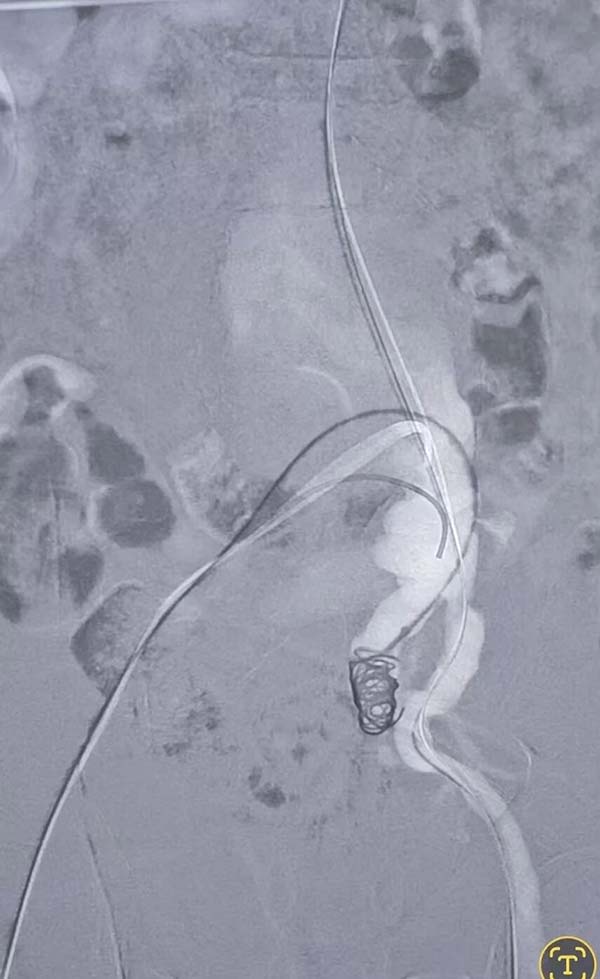

术中造影间巨大腹主动脉瘤和髂动脉瘤破裂

在手术台上,宋盛晗带领医师王盛兴、王杨、王峰密切配合,果断实施腹主动脉瘤腔内隔绝术。整个手术过程紧张而有序,仅用1个半小时便顺利完成。团队的高效协作和精湛技术,快速止住了出血,并使用微创技术将破裂腹主动脉瘤这个“炸弹”成功“拆解”。术后患者转入重症医学科接受进一步抢救治疗。

弹簧圈栓塞